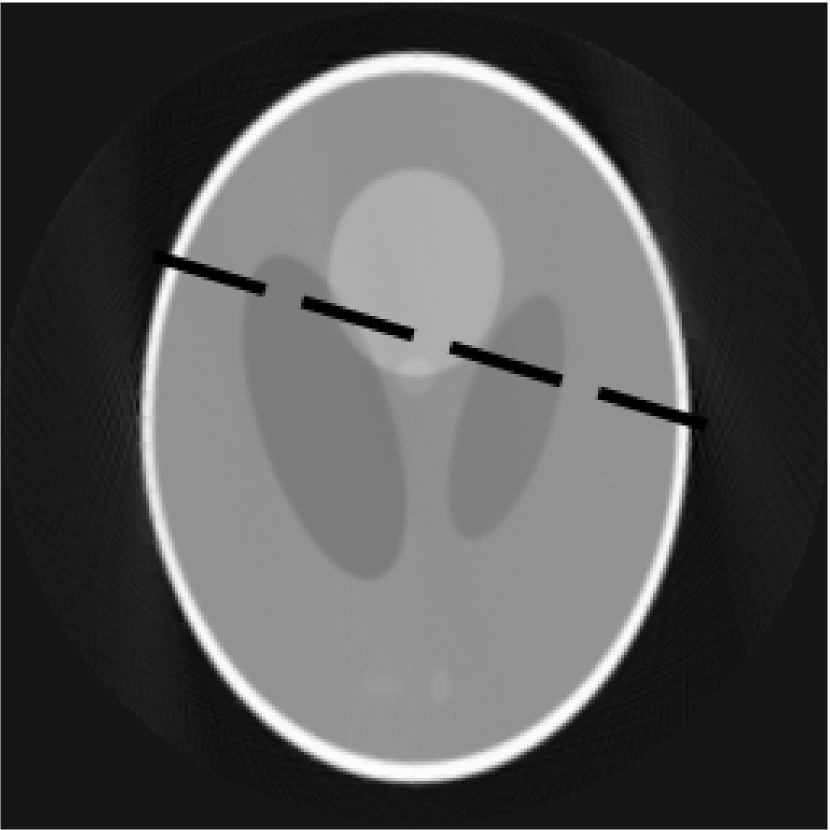

The simplest idea is to divide pixel-wise image, produced by the decomposition algorithm, by image obtained from the FDK. This gives a relative difference between images. An example of using this method is shown in figures 4a, 4b and 4c. FigureΒ 4a is a slice reconstructed by the FDK, figureΒ 4b - by the FDK-OD and figureΒ 4c shows a result of pixel-wise division of these 2 slices.

Tests with Shepp-Logan phantom show that decomposition almost doesnβt affect uniform regions of slice, thus blurs edges and the borders. Skip of 1 decimation stage significantly decreases the blur and helps to preserve sharp borders. This can be seen on the profile comparison (figureΒ 6) for the objects reconstructed with FDK and with our algorithm (5 stages of decomposition, 1 decimation stage is skipped). Corresponding slices are shown in the figures 5a and 5b.